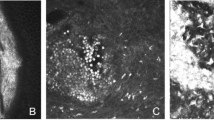

The representative examples of accurately classified corneal pathology grades by ResNet50 across independent test sets are shown in Fig. 4. Whereas Fig. 5. Depicts the examples of misclassified corneal grades. Furthermore, randomly selected images (one from each grade) with classes predicted by ResNet50 were used to further validate the results via Scheimpflug imaging (using Pentacam HR), as shown in Fig. 6.

Demonstration of true and predicted corneal pathology grades for SM-exposed rabbit corneas. The first row shows the true pathology grades (healthy, mild, moderate, and severe), whereas the second row displays the grades predicted by the best-performing ResNet50 model. The third row presents corneal density heatmaps generated via Pentacam HR, validating the model’s predictions by illustrating corresponding changes in corneal density for each grade.